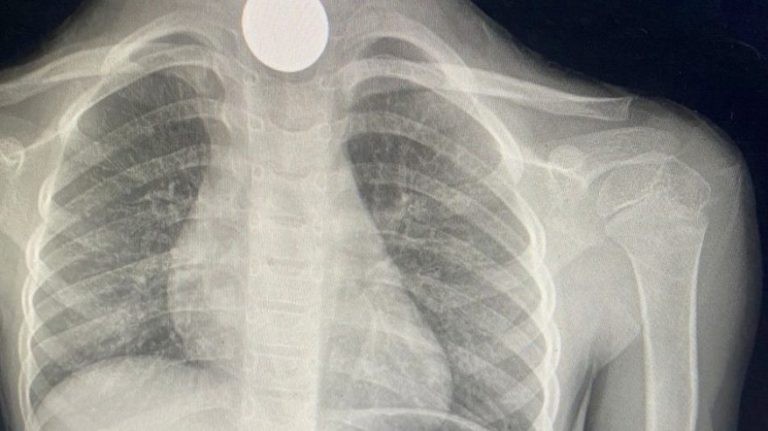

أوضحت المديرية العامة للصحة بمنطقة الجوف أن فريقاً طبيًّا نجح في إنقاذ حياة طفلة ابتلعت قطعتين معدنيتين.

وأضافت “صحة الجوف” في تغريدة على “تويتر”، أن فريقًا طبياً في مستشفى طبرجل العام تمكن من إنقاذ حياة طفلة ٥ سنوات انقطع عنها الأوكسجين وكانت تعاني من مشاكل في التنفس نتيجة ابتلاعها قطعتين معدنتين.

وأشارت صحة الجوف، إلى أنه تم استخراج القطعتين المعدنيتين بعد وصولها لقسم الطوارئ، وخرجت بحالة جيدة.